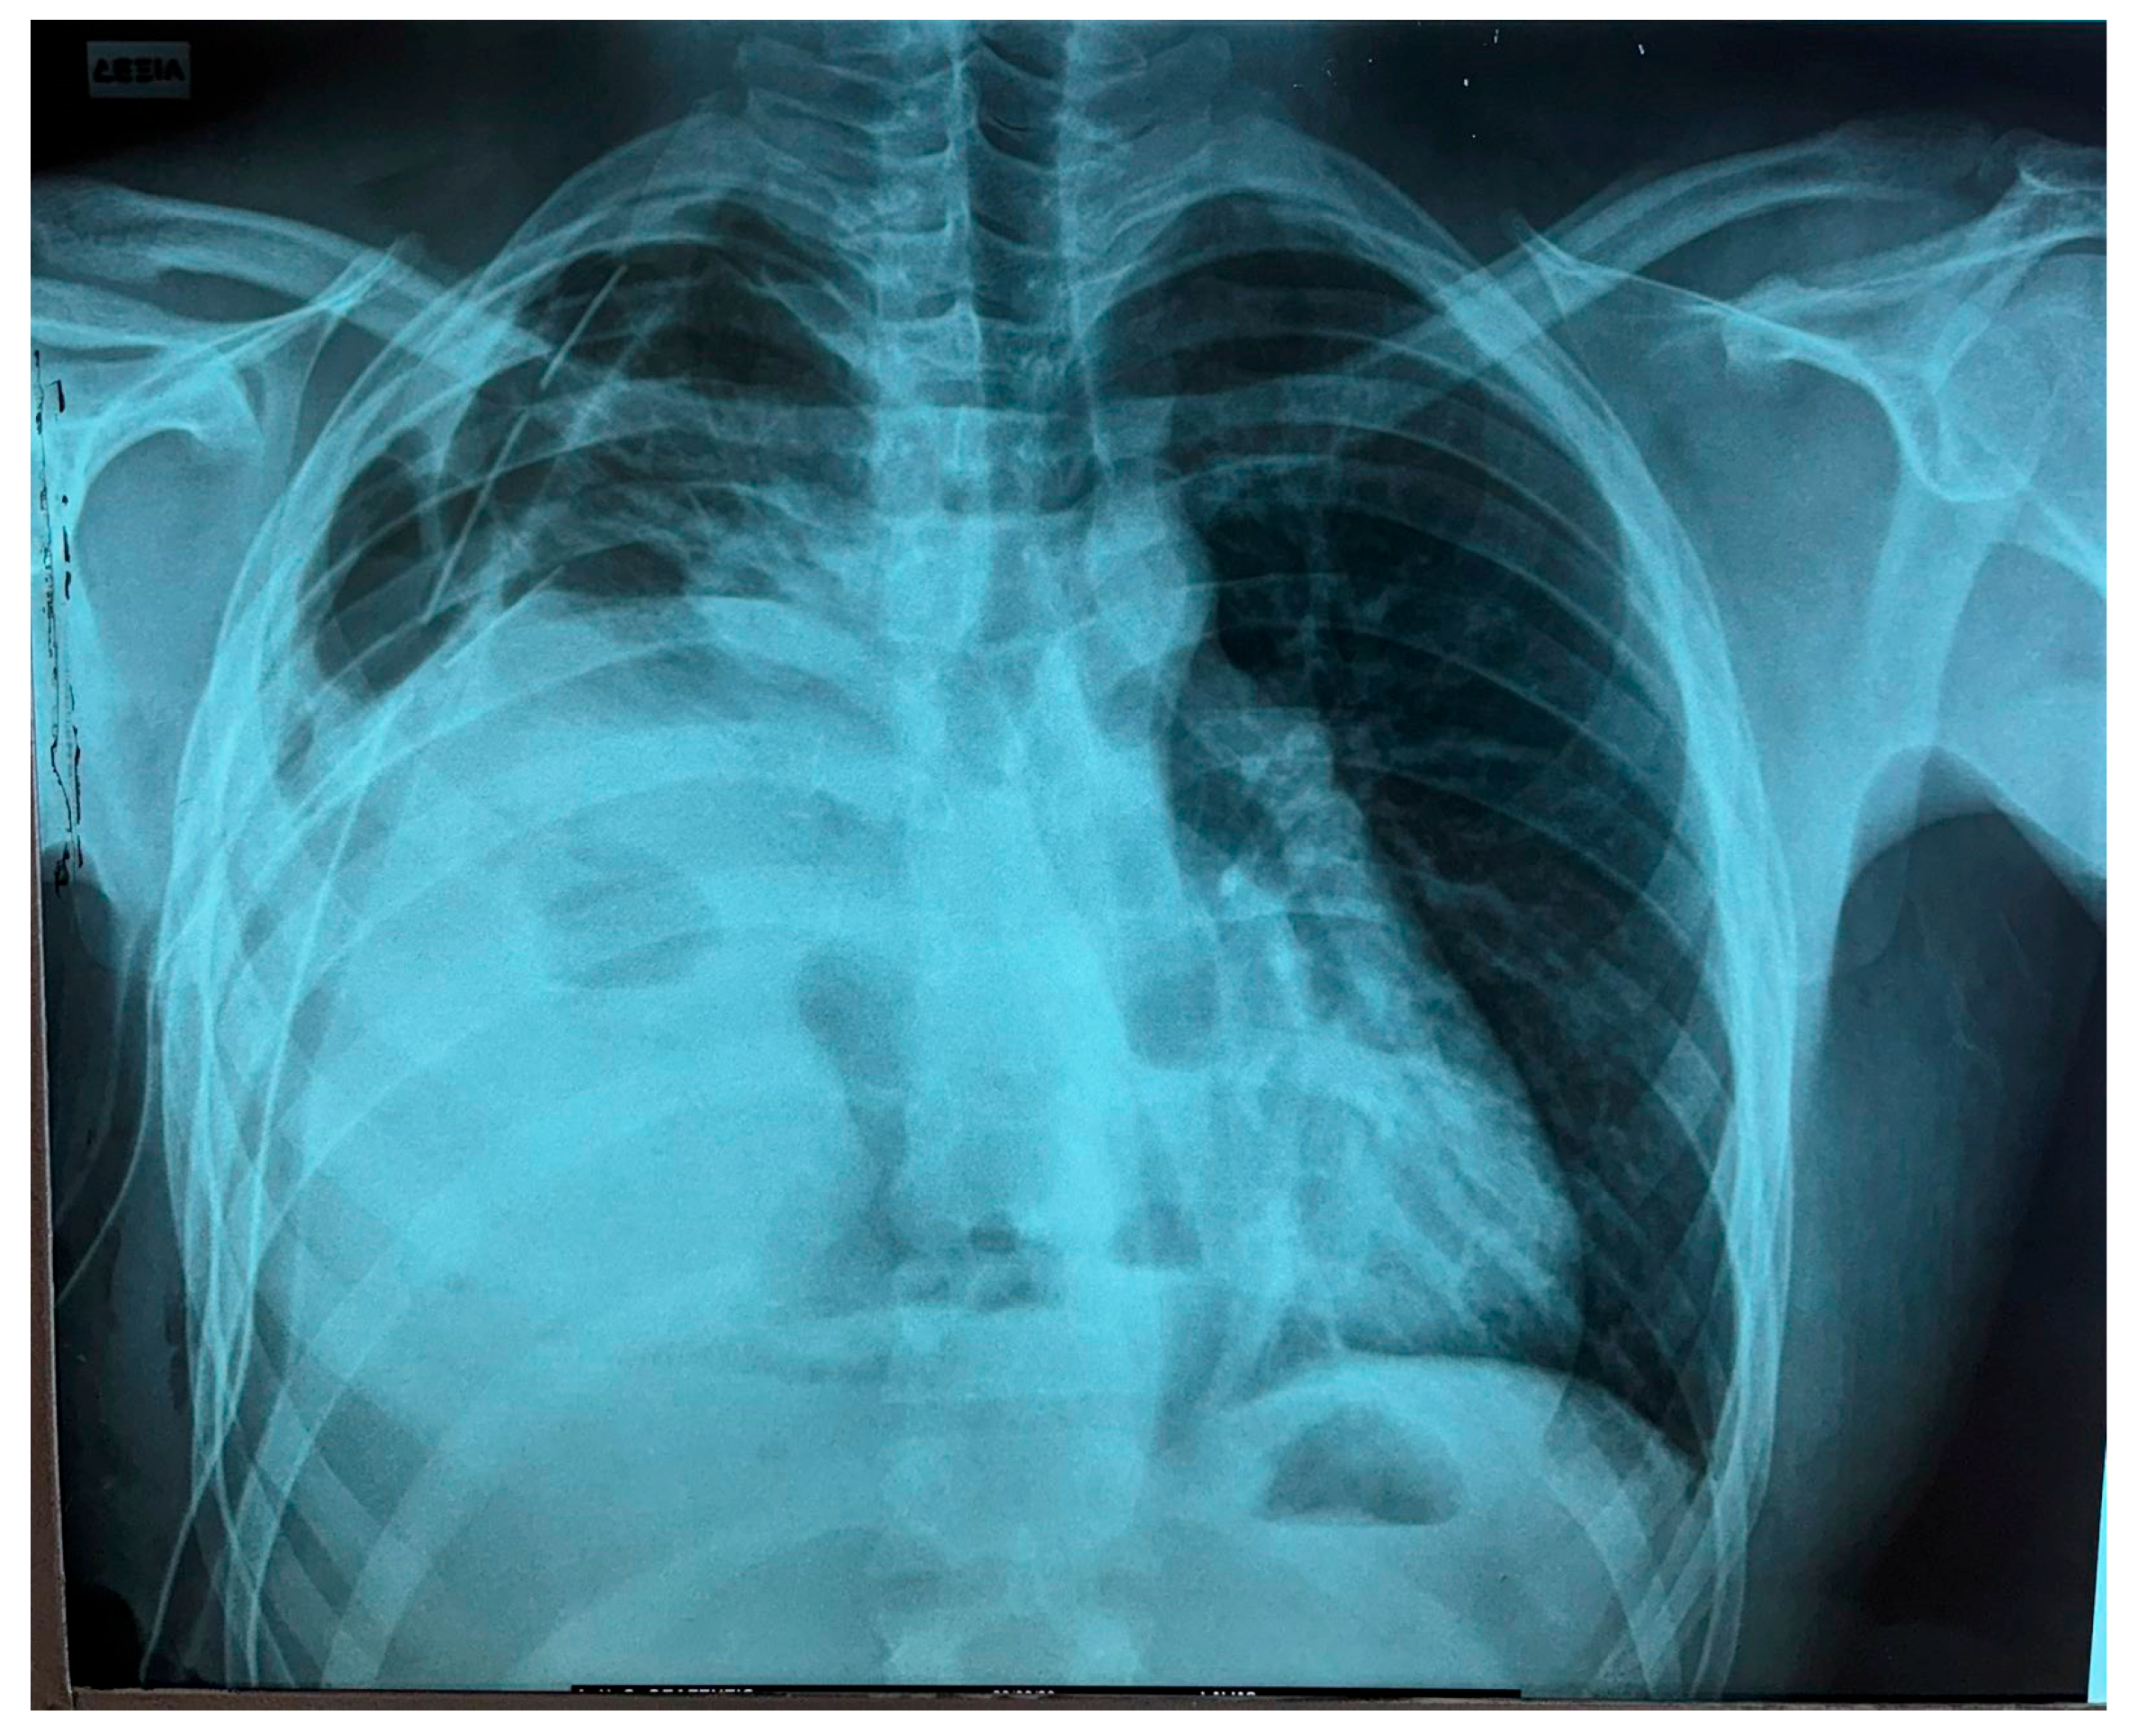

Furthermore, additional magnetic resonance imaging (MRI) provided details regarding local invasion, particularly about pericardial and vascular structures [5] (Figure 2).

The tumor’s measurements had increased (DMax: 16 cm × 9 cm × 13 cm). Intraoperatively, severe degree of atelectasis of the Right Lower Lobe (RLL) parenchyma with an additional pressure–displacement effect upon the Superior Vena Cava (SVC) and (R) heart sinus were detected. These findings were already indicated from the preoperatively performed chest MRI. Immediately postoperatively, the patient’s respiratory mechanics significantly improved, while the received tissue provided conditions for definitive histological classification and molecular analysis [10] (Figure 3).

Figure 2. Initial preoperative MRI.

Figure 3. First postoperative day X-ray control (after VATS R).